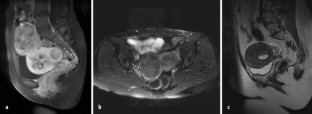

Abb. 3a–e

Abb. 5a,b

Abb. 7a–c